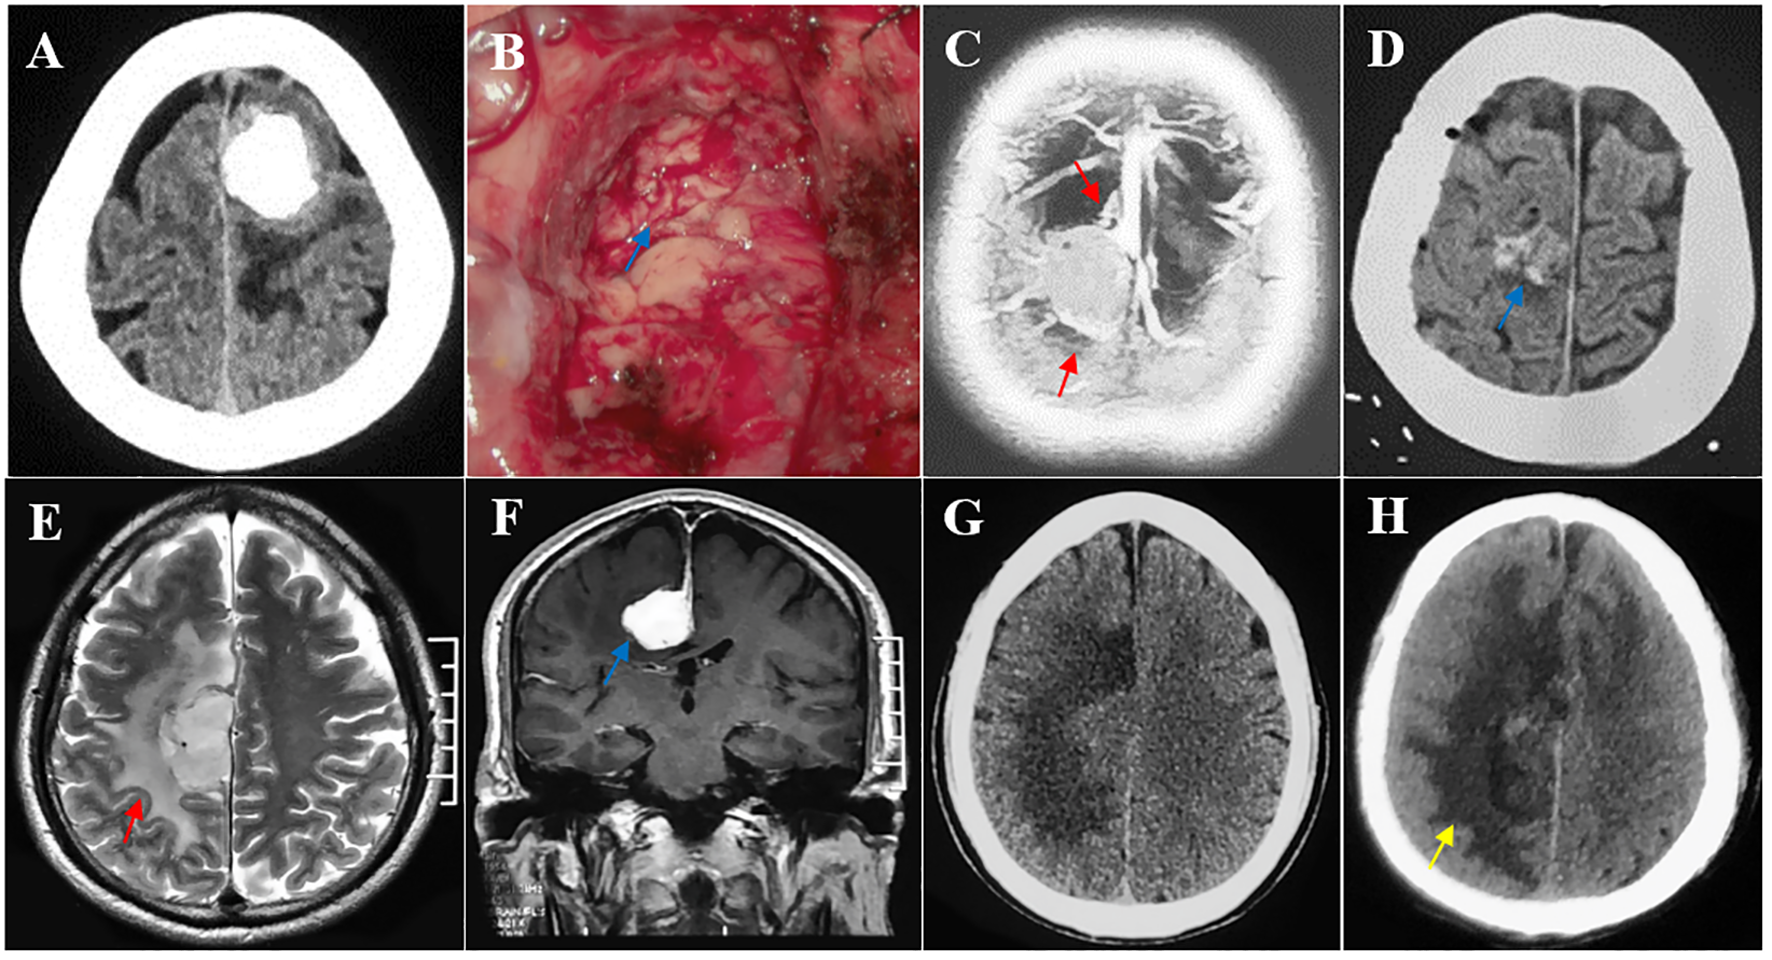

Figure 4

Multiple risk factors leading to postoperative motor decline after parasagittal/falx meningioma resection in the middle third SSS. (A, B) The tumor invading the pia mater was completely removed, and the brain-tumor interface was lost intraoperatively (blue arrow). Pathological testing revealed an atypical meningioma. (C, D) Multiple peritumoral veins (red arrow) and postoperative minor hemorrhage (blue arrow). (E–H) A deep falx meningioma (blue arrow) with obvious peritumoral edema (red arrow) and postoperative edema expanded (yellow arrow) compared with its preoperative condition.